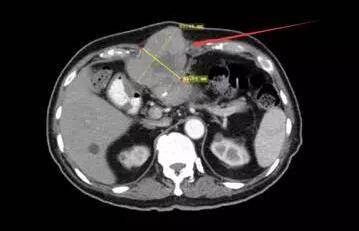

基于AFP升高以及CT结果,考虑患者肝癌复发并转移。随后患者开始接受索拉菲尼的治疗,口服,每次200mg,每天两次,持续一周后改为每次400mg,每天两次。后来,由于出现严重的手足治疗相关副作用,剂量从400mg降至200mg,依然还是一天2次。在5个月的治疗后,AFP从2751mcg/L上升到8877mcg/L,复查CT发现之前的肿块更大了。

在疾病进展、索拉菲尼治疗失败后,患者及家属决定做最后一搏,尝试使用Keytruda进行治疗,剂量为2mg/kg,每3周注射一次。在6个周期后,复查CT结果发现肿块组织从8*6cm缩小到4*1.6cm,AFP从8877mcg/L降至1.7mcg/L. 效果让人非常惊讶,而且患者目前耐受Keytruda治疗,没有出现什么严重的副作用。

治疗前CT影像